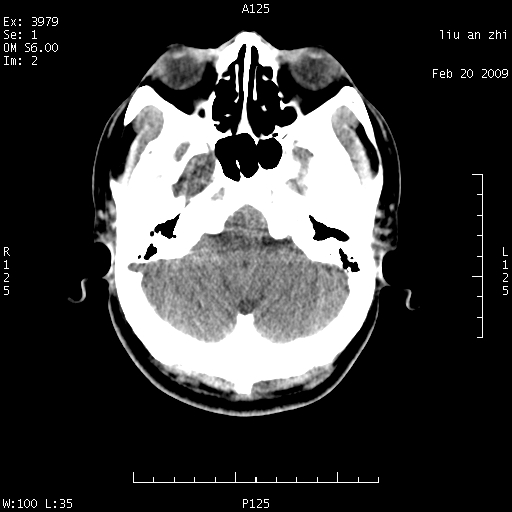

患者:男,32岁 被打伤后3天,自感头昏头痛作头颅ct检查。请大家看一下想什么??

请注意小脑幕!!!

考虑左侧天幕硬膜下血肿。

密度不够,不能诊断sah.正常小脑幕密度可稍高。

左侧天幕硬膜下血肿